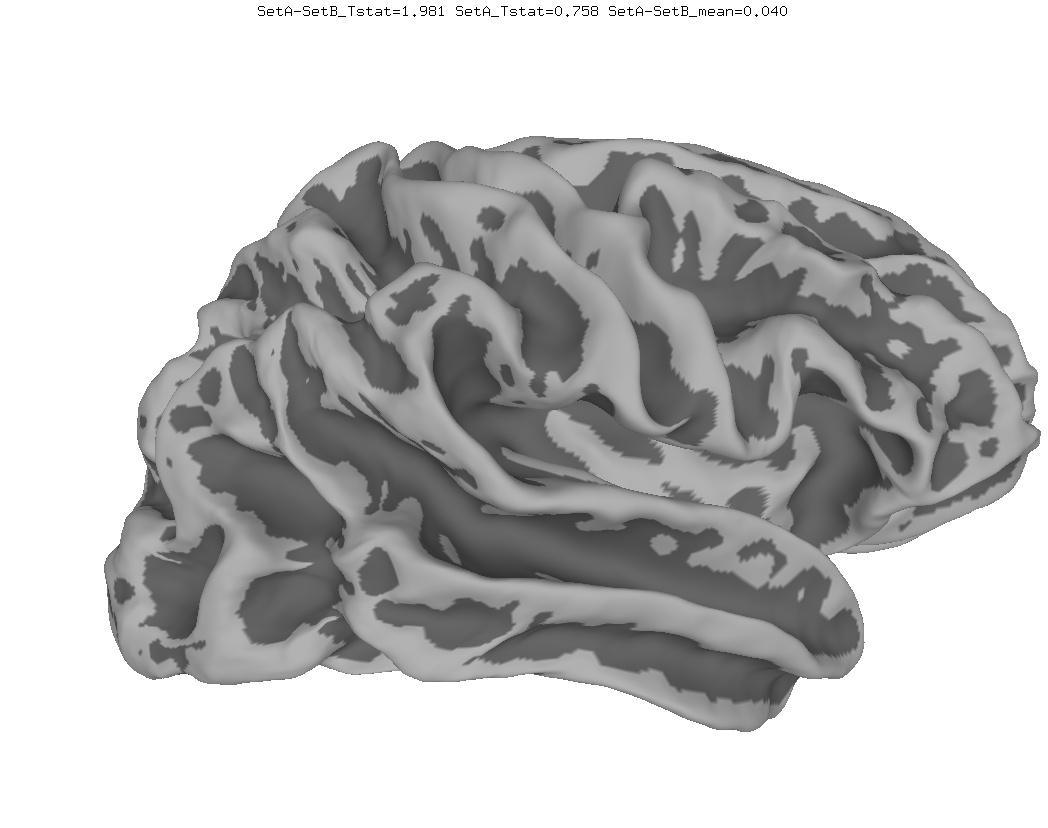

Anatomical Data

New

Old

In March 2017, the AFNI team discovered a bug in the MapIcosahedron program. Here is a comparison of group average results with the old and new (fixed) versions. If you have old surface averages and would like to fix them, you can use a script like this to create new surfaces, then re-run your surface averaging processing stream.